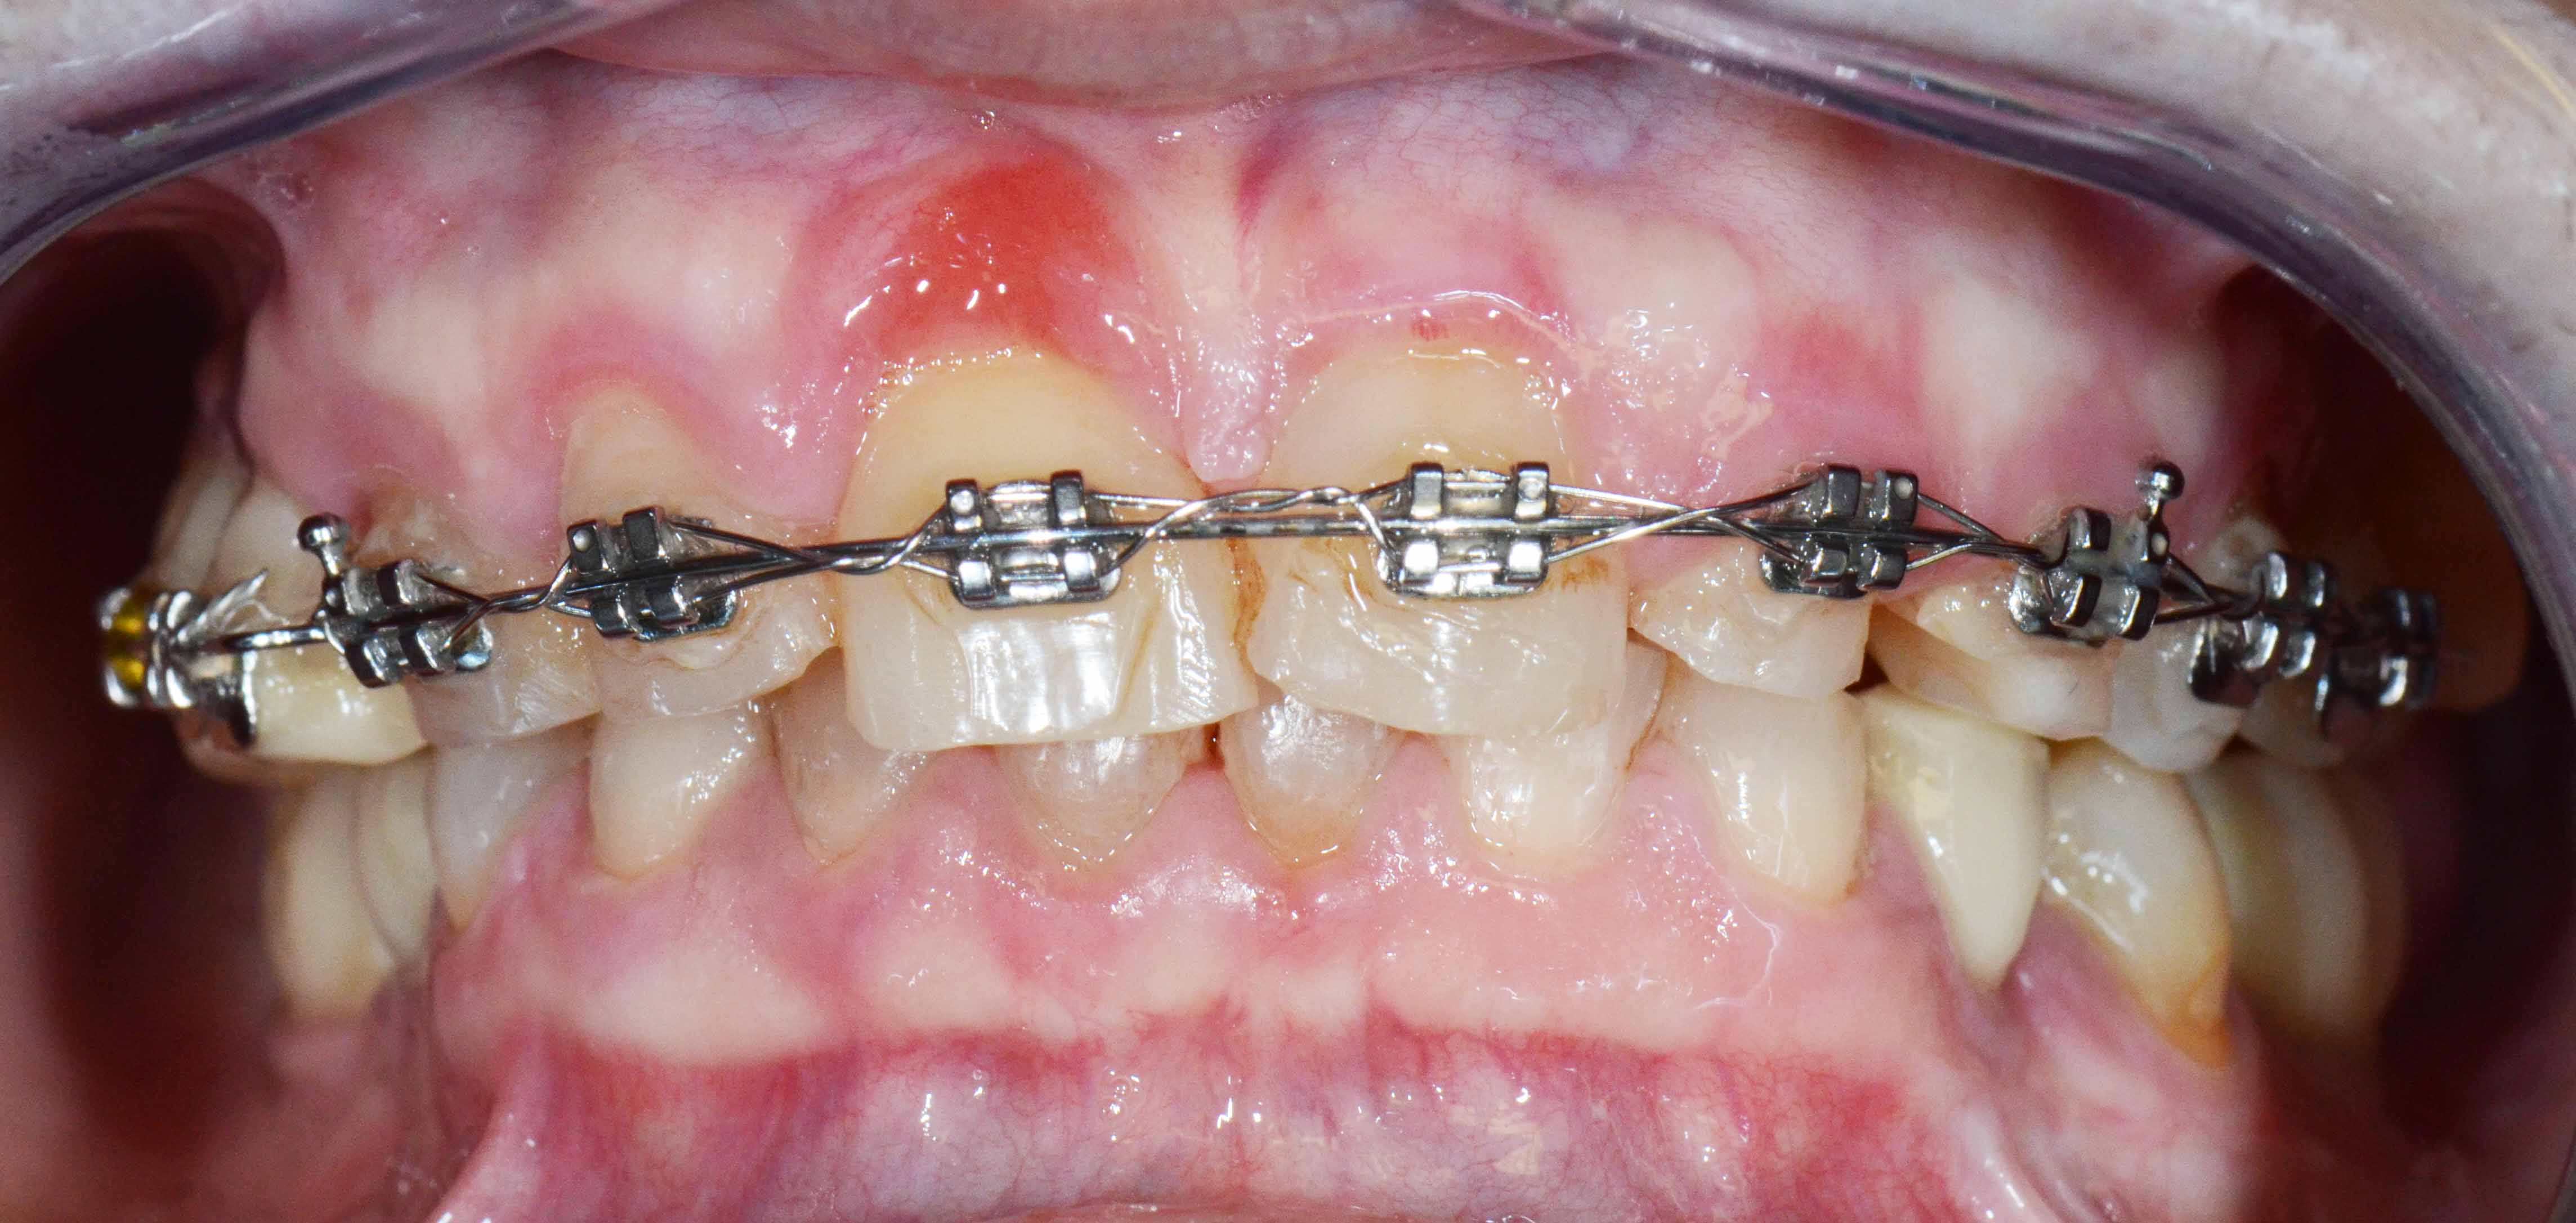

Reabilitação Complexa - Tratamento

Mantiveram-se os dentes naturais remanescentes que tinham bom prognóstico e com Aparelho Ortodôntico fixo foram corrigidas as suas posições.

Posteriormente foi feita cirurgia para colocação de alguns Implantes.